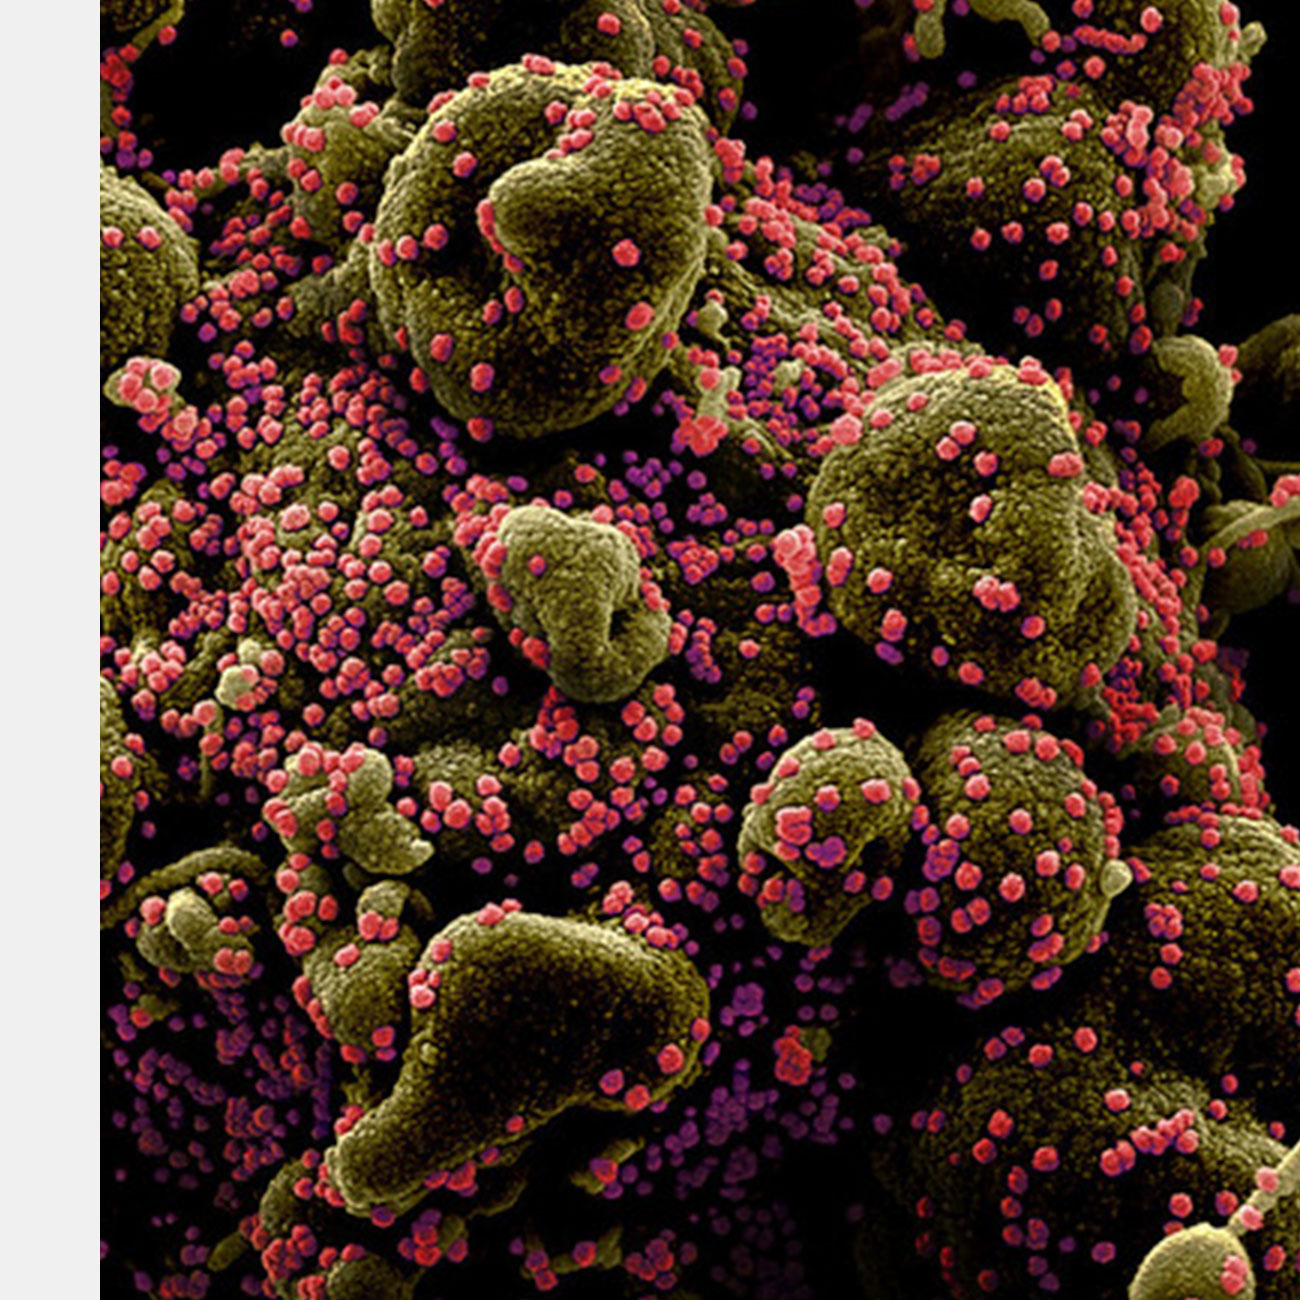

ВОЗ одобрила вакцину от COVID-19 компании Novavax. Препарат Nuvaxovid стал десятым одобренным организацией для экстренного использования. Эту же вакцину под названием Covovax индийского производства организация одобрила накануне. Кроме того Nuvaxovid рекомендовали для одобрения в Европе.

Исследователи из Франкфуртского университета имени Гёте провели испытания, показавшие нулевой уровень нейтрализации нового варианта коронавируса «Омикрон». Такие данные были получены у пациентов, получивших две дозы вакцин Moderna и BioNTech.

Американские медики проанализировали данные 780 тысяч ветеранов и выяснили, что коронавирусные вакцины от Pfizer/BioNTech, Moderna и Johnson & Johnson к концу 2021 года стали хуже защищать от заражения, чем в начале года. Особенно это заметно для препарата, разработанного Johnson & Johnson. При этом все вакцины продолжают защищать от смерти от ковида с эффективностью в 70-80 процентов. Работу опубликовали в Science.